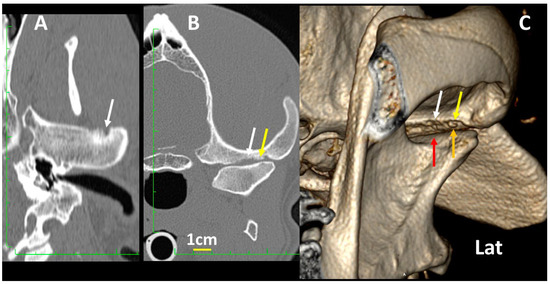

3.4. A Pictorial Essay of 3DVR Images in Some Pathological Cases